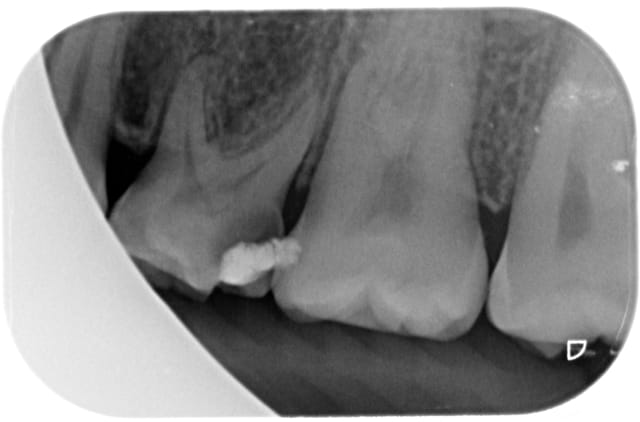

je reçois ce jour cette nouvelle patiente trisomique qui présente des agénésies multiples.

le traitement odf est phase de contention

55,65,75 et 85 ont été conservées

mais pour 65 75 et 85 c'est endo je pense

Le délabrement sur 65 et encore plus sur 75 seront plus qu'occluso-proximaux

La restauration directe ou indirecte ne concernera que 85 dans le meilleur des cas.